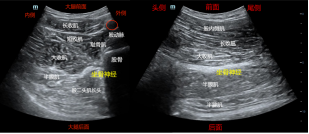

①坐骨神经短轴成像,股骨小转子水平,即腹股沟横纹处(皱褶)远端5-8cm,探头与股骨垂直,找到股骨和找到大收肌,在大收肌的后面寻找椭圆形或圆形的高亮回声,就是坐骨神经。平面内法,一般从探头的大腿外侧端进针,但也可从探头的大腿内侧端进针,药物注射在坐骨神经周围。避免穿通损伤坐骨神经,同时外侧进针时还要避免损伤股动脉,因为股动脉在进针的路径上。

②坐骨神经长轴成像,股骨小转子水平,腹股沟横纹(皱褶处)远端5-8cm,寻找到坐骨神经的短轴后,探头旋转90°,在大收肌的后面可见条索状高亮回声,就是坐骨神经。平面内法,从探头的大腿尾侧端进针,药物注射在坐骨神经周围,超声可见药液扩散。